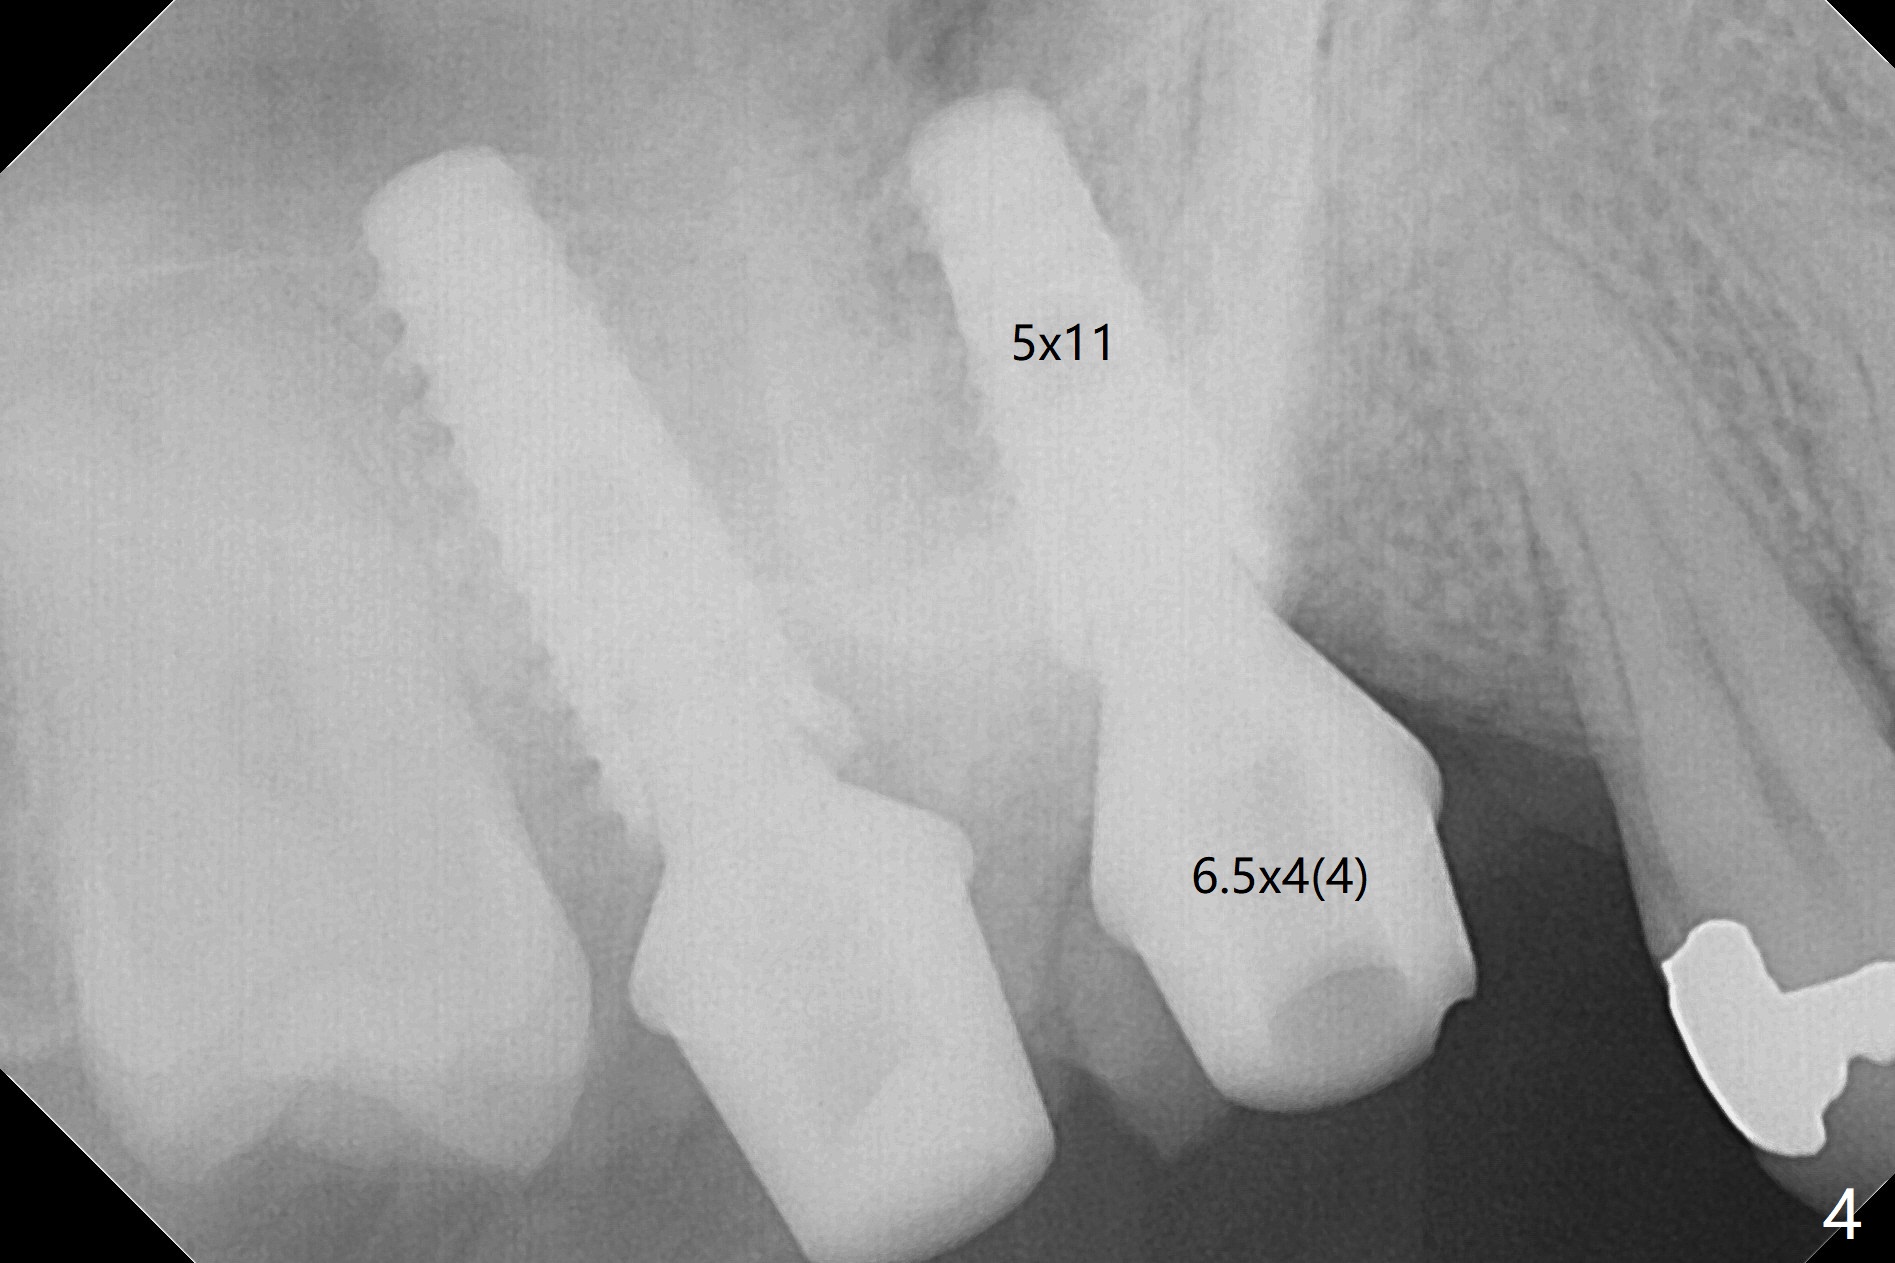

The gingiva at #2 adapts to the abutment 3.5 months post placement (Fig.1). After incision, osteotomy at #3 is initiated by free hand, which is found off (Fig.2 (red line: normal trajectory)). After repositioning osteotomy, a 4.5x11 mm dummy implant is placed with minor trajectory issue (Fig.3). Following further adjustment, a 5x11 mm implant is placed with relatively normal axis; a 6.5x4(4) mm abutment is inserted. Autogenous bone, Vanilla and Osteogen are placed distobuccally (Fig.4). Guided surgery should be more efficient and precise. There is no implant thread exposure 9 and 5 months postop at #2 and 3, respectively (Fig.5,6). The mesial wall of the crown at #2 is thin, having a crack line. The crowns at #2 and 3 are cemented with RelyX Ultimate Adhesive Resin Cement bonding. If the crown fractures, change the abutment (6.5x5.7(2) mm) to the one with smaller diameter (4.5 or 5.0 mm), or trim the abutment mesially heavily. Guided surgery or stent should prevent the potential complication.